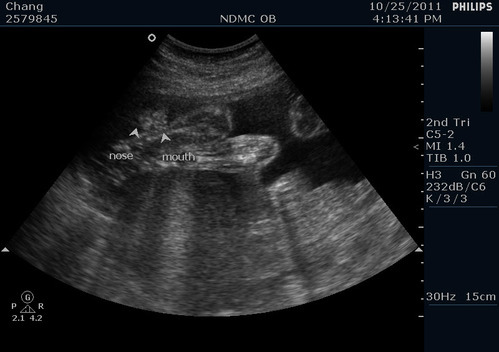

寶貝的豐唇!醫生說沒有兔唇喔! 寶貝全程都嘴開開睡覺啦~

寶貝的鼻子~跟兩個鼻孔XD